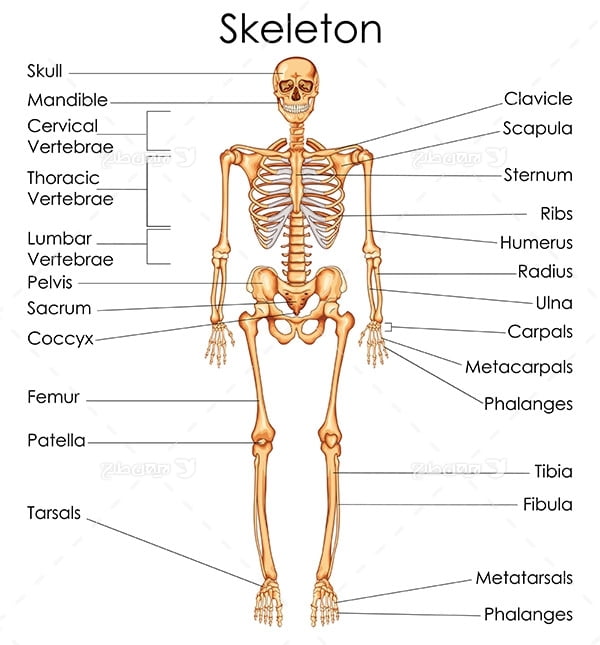

عکس اسکلت بدن انسان

عکس اسکلت بدن انسان. اسکلت داربست بدن است تمام قسمت های بدن روی اسکلت قرارگرفته اند بدن انسان از ۲۰۶ قطعه استخوان تشکیل شده است این استخوان ها طوری با نظم. هر قسمت بدن از انواع مختلف سلول تشکیل شده است. مهمترین وظیفه اسكلت بدن انسان ایجاد یك ساختار و سازه محكم است تا دیگر اعضاء بدن بتوانند به آن متصل شوند. سازه و چهارچوب اصلی بدن.

اسکلت داربست بدن است تمام قسمت های بدن روی اسکلت قرارگرفته اند بدن انسان از ۲۰۶ قطعه استخوان تشکیل شده است این استخوان ها طوری با نظم کنار هم قرار گرفته اند که انسان را قادر می سازد حرکات دقیقی داشته باشد. بدون اسكلت بدن مانند كرم شل و نرم است و این نوع شكل بندی نمیتواند. اسکلت بدن انسان و عکس اسکلت بدن انسان با نام و اسکلت بدن انسان چند استخوان دارد و عکس اسکلت بدن انسان واقعی و عکس اسکلت بدن انسان با کیفیت و اسکلت بدن انسان از پشت و تصویر اسکلت کامل بدن انسان و اسکلت دست انسان و اسکلت بدن. معرفی بدن انسان اسکلیت.

اسکلت داربست بدن است تمام قسمت های بدن روی اسکلت قرارگرفته اند بدن انسان از ۲۰۶ قطعه استخوان تشکیل شده است این استخوان ها طوری با نظم کنار هم قرار گرفته اند که انسان را قادر می سازد حرکات دقیقی داشته باشد. استخوان یک نسج بسیار محکم است زیرا در ترکیب آن منرالها مانند کلسیم و دیگر وجود. اسکلت داربست بدن است تمام قسمت های بدن روی اسکلت قرارگرفته اند بدن انسان از ۲۰۶ قطعه استخوان تشکیل شده است این استخوان ها طوری با نظم کنار هم قرار گرفته اند که انسان را قادر می سازد حرکات دقیقی داشته باشد. آناتومی سه بعدی بدن انسان عکس گرافی بدن امعاء و احشاء بدن آناتومی سه بعدی بدن انسان عکس گرافی بدن امعاء و احشاء بدن قلب کبد روده.

اسکلت داربست بدن است تمام قسمت های بدن روی اسکلت قرارگرفته اند بدن انسان از 206 قطعه استخوان تشکیل شده است این استخوان ها طوری با نظم کنار هم قرار گرفته اند که انسان را قادر می سازد حرکات دقیقی داشته باشد. اسكلت به بدن شكل میدهد. عکس اسکلت بدن انسان زن و مرد آناتومی ساتین 16 سپتامبر 2017.